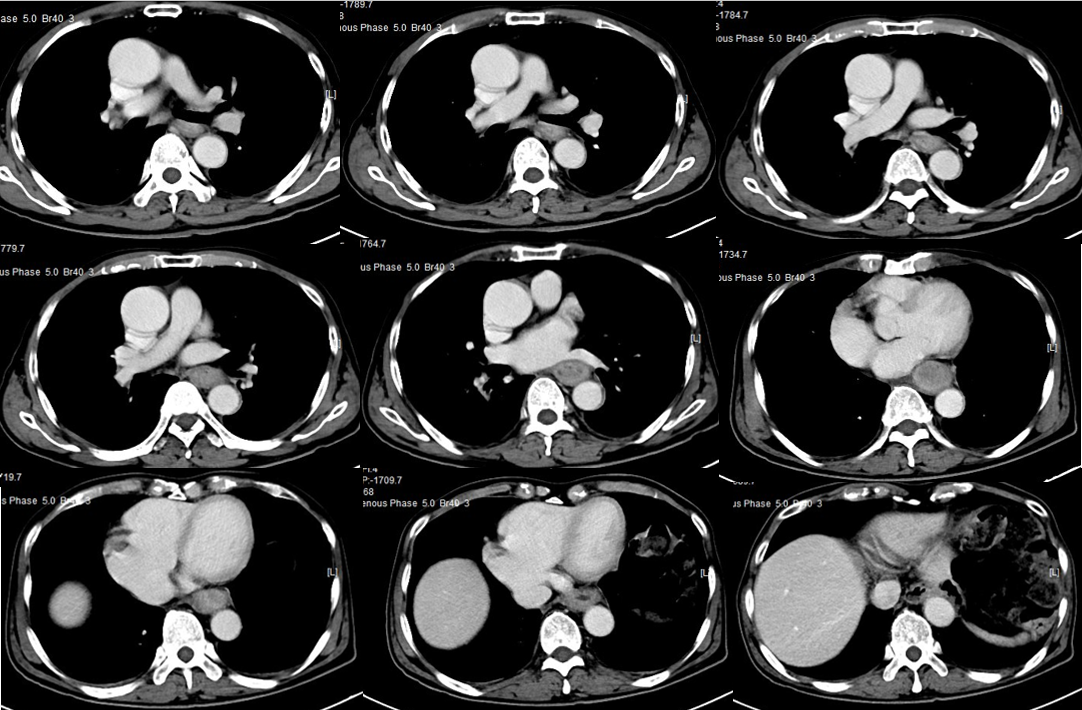

2018-10-09 食管中下段管壁增厚

2018-10-09左上腹系膜区结节灶

PET/CT(2018-10-22):食管中下段管壁增厚FDG代谢增高,吻合口下方肠壁FDG代谢增高灶;左上腹系膜区多发FDG代谢增高灶,考虑多发转移;后腹膜区及右侧髂血管旁多发小淋巴结FDG代谢轻度增高,倾向转移淋巴结。

诊断:食管MT(累及空肠)(T3N0M1)IV期